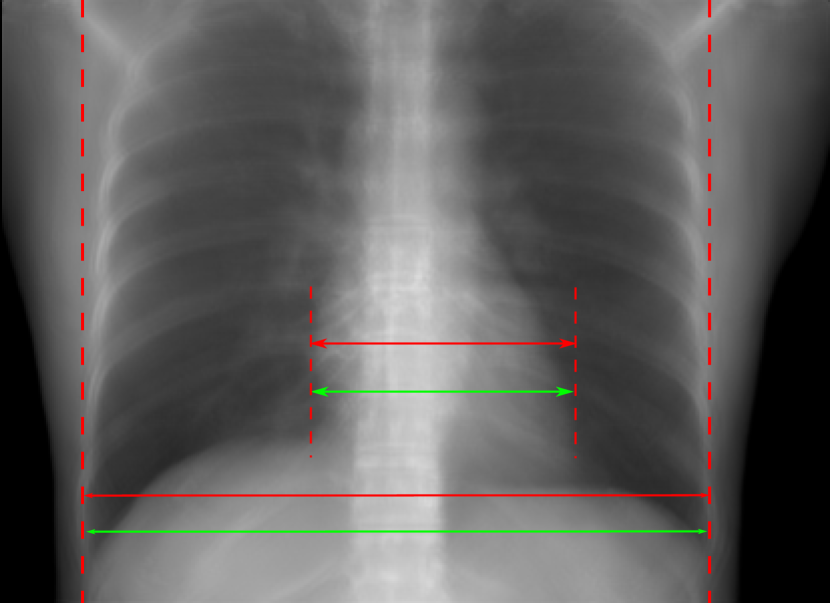

5.1 Chest Data

Refer to caption

(a) Reference

(b) 0superscript00^{\circ} perspective

(c) (b)-(a)

0.4237, -, -

0.4002, 17.01, 0.6532

Pix2pixGAN

(d) 0superscript00^{\circ} Cartesian

(e) 0&180superscript0superscript1800^{\circ}\&180^{\circ} Cartesian

(f) 0&180superscript0superscript1800^{\circ}\&180^{\circ} polar

0.4303, 7.08, 0.8535

0.4214, 5.37, 0.9098

0.4240, 3.83, 0.9536

(g) (d)-(a)

(h) (e)-(a)

(i) (f)-(a)

TransU-Net

(j) 0superscript00^{\circ} Cartesian

(k) 0&180superscript0superscript1800^{\circ}\&180^{\circ} Cartesian

(l) 0&180superscript0superscript1800^{\circ}\&180^{\circ} polar

0.4272, 10.92, 0.8222

0.4281, 9.37, 0.8424

0.4248, 8.12, 0.8859

(m) (j)-(a)

(n) (k)-(a)

(o) (l)-(a)

Figure 10: Perspective deformation learning in one exemplary patient case for chest X-ray imaging. The maximal horizontal cardiac diameter and the maximal horizontal thoracic diameter in (b) and (d)-(f) are indicated by the horizontal red lines, while those in the reference image (a) are green lines. The cardiothoracic ratio, RMSE, and SSIM for each image is displayed in its corresponding subcaption.

TABLE II: Quantitative evaluation of different methods on chest data.

Method Metric 0superscript00^{\circ} input 0superscript00^{\circ} 0&180superscript0superscript1800^{\circ}\&180^{\circ} 0&180superscript0superscript1800^{\circ}\&180^{\circ}

perspective Cart. Cart. polar

Pix2pix RMSE 18.68 11.88 7.90 4.98

GAN SSIM 0.6401 0.8103 0.8944 0.9493

Trans RMSE 18.68 17.21 12.12 13.06

U-Net SSIM 0.6401 0.7744 0.8950 0.8899

The results of one patient in chest X-ray imaging are displayed in Fig. 10, where the cardiothoracic ratio is assessed as an exemplary clinical application [32]. In the reference image (Fig. 10(a)), the maximal horizontal cardiac diameter (MHCD) and the maximal horizontal thoracic diameter (MHTD) are indicated by two green horizontal lines. Its cardiothoracic ratio is 0.4237. In the 0superscript00^{\circ} perspective projection image (Fig. 10(b)), all the anatomical structures can be visualized with fine resolution. However, due to perspective deformation, anatomical structures, e.g. the ribs and the spine, are deformed. The deformations are visualized better in the difference image Fig. 10(c). Compared with the ribs and the spine, the heart has less deformation as its location is closer to the isocenter. In Fig. 10(b), the MHCD and the MHTD are indicated by two red horizontal lines, while the green lines are those of the reference image. While the MHCD has changed little from 10.47 cm to 10.16 cm, the MHTD has changed considerably from 24.71 cm to 25.40 cm. As a consequence, the cardiothoracic ratio becomes 0.4002, which is below the normal range of 0.42 - 0.50 [32]. The result of learning perspective deformation from 0superscript00^{\circ} single view is displayed in Fig. 10(d), where the MHCD and the MHTD are 10.63 cm and 24.71 cm, respectively. The MHTD of Fig. 10(d) is the same as that of the reference image. This is also reflected by the difference image Fig. 10(g), where the lower ribs have small errors. However, the upper ribs as well as the spine still have considerable errors. The results of perspective deformation learning from 0&180superscript0superscript1800^{\circ}\&180^{\circ} views in Cartesian and polar coordinates are displayed in Fig. 10(e) and Fig. 10(f), respectively. The measured MHCDs and MHTDs in these two images are very close to the reference ones. Hence, their cardiothoracic ratios, 0.4214 and 0.4240 respectively, are close to the reference ratio as well. In the difference images (Fig. 10(h) and Fig. 10(i)), the errors of ribs and spine decrease as their boundaries are no longer apparently visible. Nevertheless, Fig. 10(i) has less error than Fig. 10(h), achieving the smallest RMSE value of 3.83. The quantitative evaluation of all the 162 testing datasets is displayed in Tab. II, where learning perspective deformation from two complementary views in polar coordinates achieves the least RMSE 4.98 and highest SSIM 0.9517, demonstrating the superiority of learning perspective deformation from two complementary views in polar coordinates.

The TransU-Net results are displayed in Figs. 10(j)-(l). Compared with their corresponding Pix2pixGAN results, the TransU-Net prediction images are more blurry, although the same perceptual loss is used. The error images in Figs. 10(m)-(o) indicate that TransU-Net reduces perspective deformation better with complementary views than a single view. The quantitative evaluation in Tab. II shows that TransU-Net cannot effectively reduce perspective deformation with a single view. With complementary views in both Cartesian and polar coordinate systems, TransU-Net achieves comparable performance, which is still considerably worse than that of Pix2pixGAN. The inferior performance of TransU-Net to Pix2pixGAN on the chest data is potentially caused by the repetitive nature of the segmental rib anatomy, which leads TransU-Net to be ineffective in extracting position-dependent features.